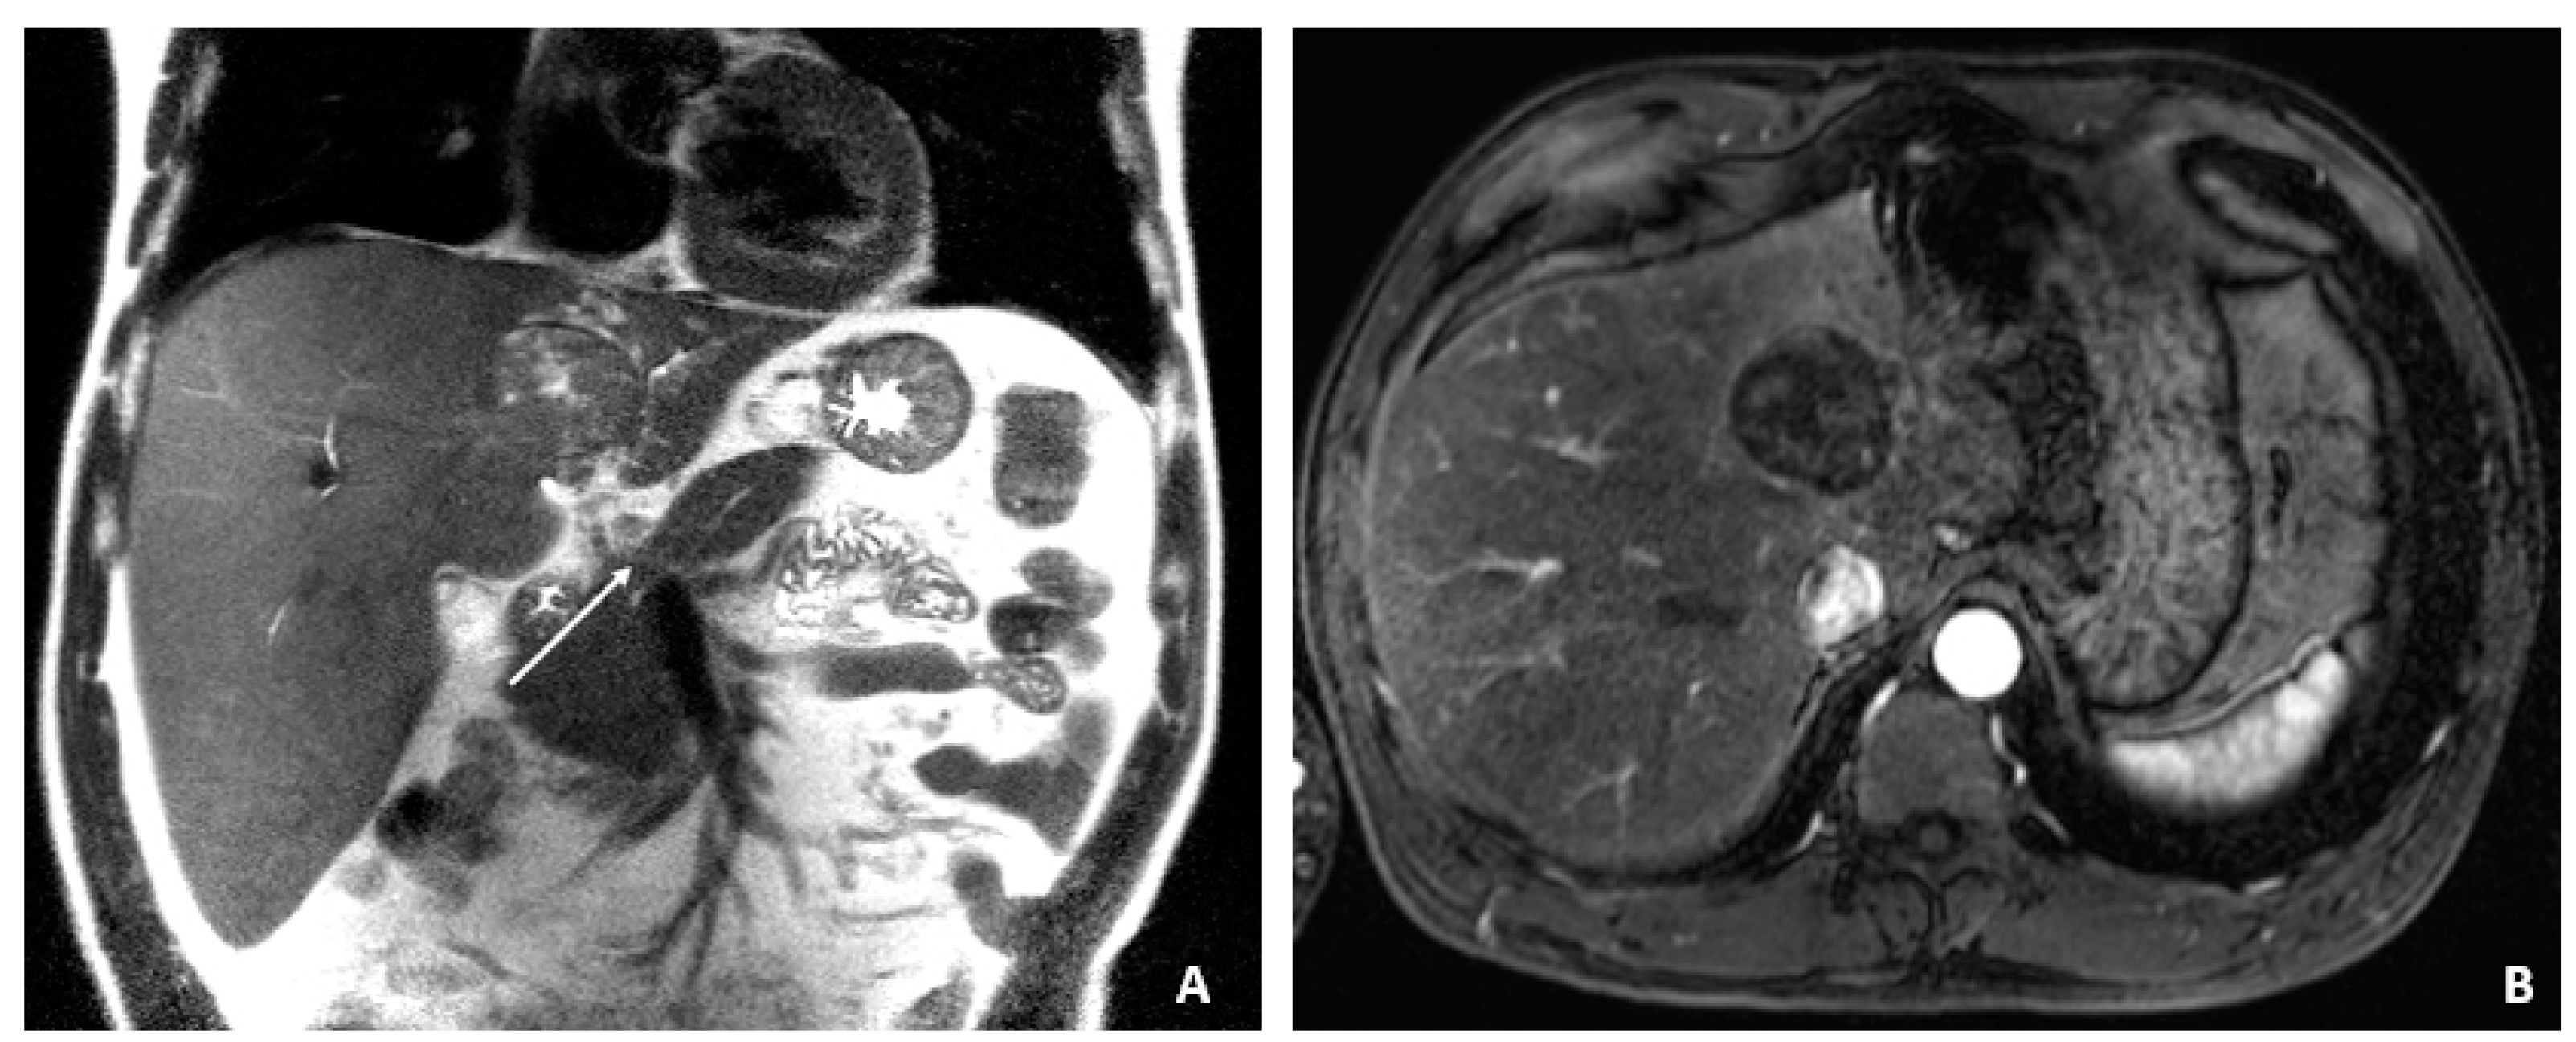

A 50-year-old male was diagnosed with CHB at age 40. With lamivudine treatment for 3 years, he achieved HbsAg seroconversion to anti-HBs and lamivudine was discontinued. Table 4 outlines his course. Five years later, on a follow up examination he was found to have HBV DNA 847 copies/mL, ALT 33 IU/L, and AFP 20.5 ng/mL. An MRI (December 2009) showed a 5 cm lesion consistent with HCC (Figure 1A,B). Repeat AFP was 17.8 ng/mL at time of HCC diagnosis, and AFP-L3% was 75.6. He underwent transarterial chemoembolization (TACE) with successful resolution (Figure 2A,B) and restarted lamivudine. The AFP remained at 3.0 ng/mL, and the MRI showed no evidence of HCC the following year. Two years after initial treatment, the AFP increased to 5.9 ng/mL with 57.5% L3. The MRI next month showed recurrent HCC at the treated site (Figure 3). The patient underwent laparoscopic radiofrequency ablation and therasphere treatment.

Figure 1.

MRI at the time of diagnosis of HCC (December 2009). (A) The coronal T2-weighted image shows a mildly heterogeneous mass in the left hepatic lobe (arrow), corresponding to hepatocellular carcinoma. (B) The axial T1-weighted fat-suppressed arterial-phase postcontrast image shows faint foci of hyperenhancement within the lesion, characteristic of HCC.